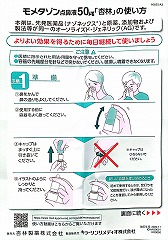

22.10.29 鼻炎薬吸引 モメタゾン点鼻液50μg 噴霧用 5mg10g 杏林 56噴霧用